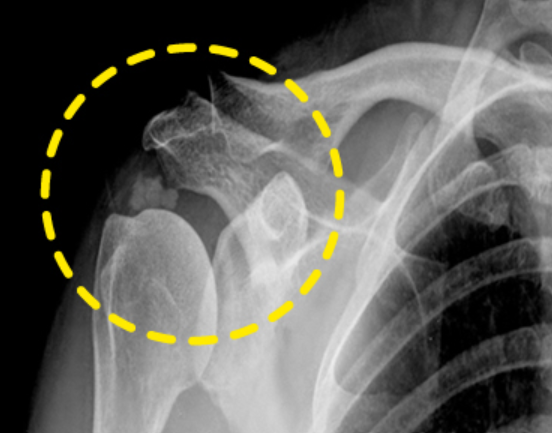

어깨통증 원인 3. 유착성 관절낭염

어깨통증 원인 세 번째는 유착성 관절낭염입니다. 팔을 움직일 때 어깨 통증이 느껴진다면 유착성 관절염 또한 의심할 수 있습니다. 유착성 관절염은 어깨 관절 주변의 막인 "피막"이 염증으로 인해 두꺼워지고 딱딱해져서 움직임이 제한되는 질환입니다. 유착성 관절염은 어깨 관절의 가동 범위를 감소시켜 팔을 들기 어렵게 하고 어깨 주변에 통증을 유발할 수 있습니다. 유착성 관절염이 진행됨에 따라 팔을 펴거나 구부리는 것과 같은 대부분의 움직임이 제한되고 어깨가 경직될 수 있습니다.

이 때는 아무리 힘을 써도 억지로 팔이 올라가지 않기 때문에 어떤 이유로 이러한 질병이 나타났는지 이유를 파악하는 것이 중요합니다. 이 때는 전문병원을 통하여 MRI와 초음파를 활용한 정밀검사를 실시하며 원인을 파악하여 원인을 개선하는 치료를 하거나 노화나 오십견으로 인한 통증인 경우 생활습관 개선, 약물치료, 재활 운동 등을 통하여 비수술적 치료를 우선적으로 실시하며 개선되지 않는다면 수술적 치료가 고려됩니다.